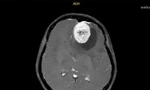

Trong quá trình bay, tổ cấp cứu tiếp tục nhận được thông tin khẩn từ Bệnh xá đảo Trường Sa Lớn về một bệnh nhân nam N.T.P. (sinh năm 1992) bị chấn thương sọ não, nghi ngờ máu tụ nội sọ. Sau hội chẩn từ xa, bệnh nhân được chỉ định vận chuyển khẩn về đất liền để theo dõi và điều trị chuyên sâu.

cap-cuu-2.jpg

Nam bệnh nhân bị chấn thương sọ não đã may mắn được kết hợp chuyển vào đất liền trên chuyến bay cấp cứu

Theo Đại úy - BS Tạ Văn Bạch, do bệnh nhân chấn thương sọ não, trực thăng phải bay thấp hơn bình thường để bảo đảm an toàn khiến thời gian bay kéo dài đáng kể. Trong suốt hành trình, kíp cấp cứu phải theo dõi sát diễn biến của cả hai bệnh nhân, xử trí kịp thời mọi tình huống phát sinh.